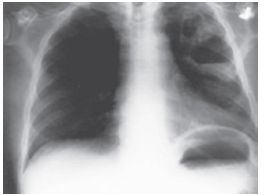

Os fenômenos retratados abaixo são manifestações características do seguinte quadro infeccioso:

Provas